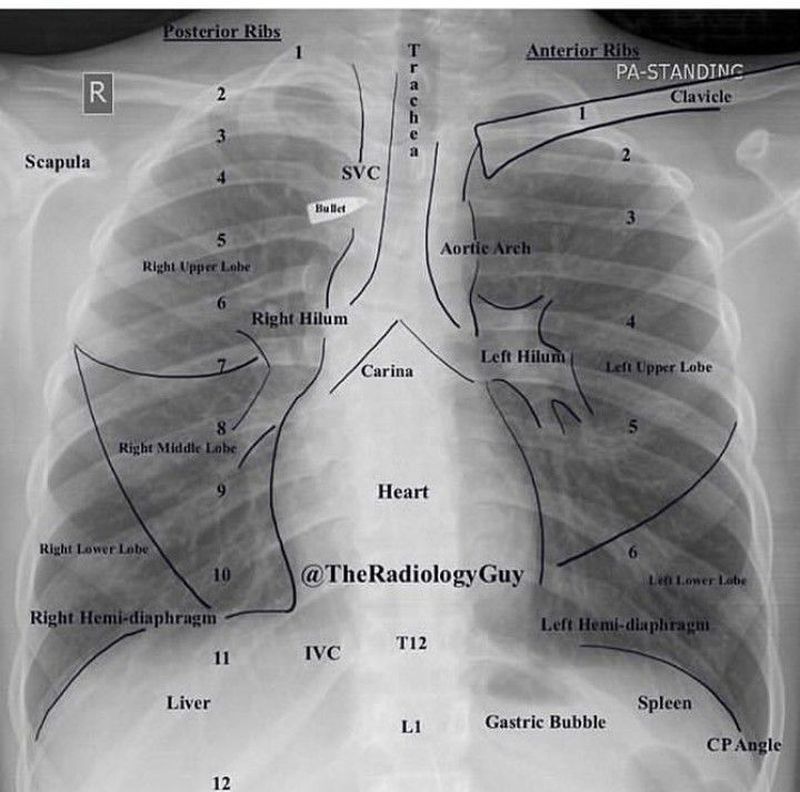

Cheat xray

Xray

Chest X-Rays